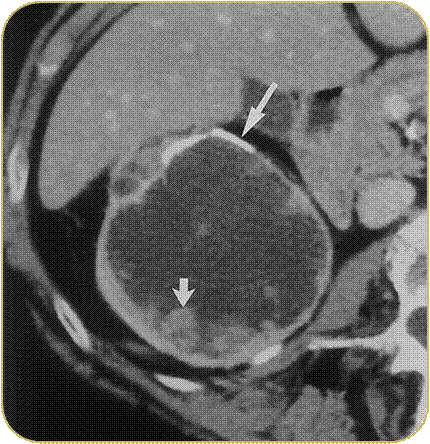

Bosniak классификация кт

Bosniak классификация кт 110 фото